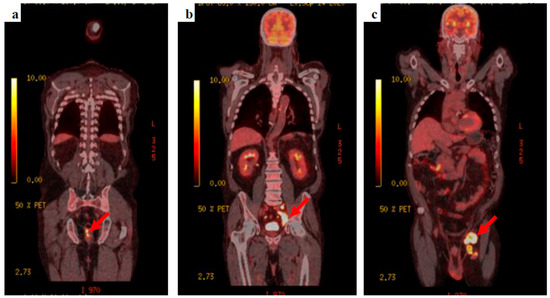

The patient’s clinical condition improved and he was keen to go home, agreeing to be referred to the neuro-oncology multidisciplinary team meeting. Whole-body fluorodeoxyglucose (FDG)-positron emission tomography (PET) was requested to find the primary tumour, showing extensive FDG-avid lymph nodes within the left groin, the left external iliac station, extending into the left common iliac group with retroperitoneal lymphadenopathy extending into the posterior mediastinum. A focus of FDG avid uptake was seen at the 6–9 o’clock position close to the anorectal junction (Figure 3).

Figure 3.

18F-FDG PET-CT images (a) the anorectal primary lesion with SUVmax 12.2, (b) deep, left external and common iliac nodal uptake, and (c) bulky, extensive, left inguinal lymphadenopathy.